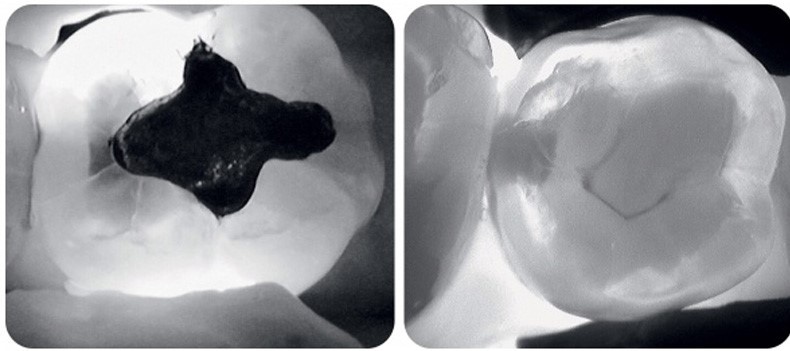

Но если что, у нас также есть классный аппарат для трансиллюминации — абсолютно безвредной процедуры, которая позволяет просветить и запечатлеть на фото зубы без использования рентгена.

Наш аппарат для трансиллюминации выглядит вот так

Процесс происходит примерно вот так

Так трансиллюминация показывает здоровый зуб

А так — кариозная полость - Вы должны приходить на профгигиену четыре раза в год.